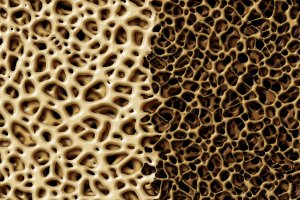

Кальцій є дуже важливим макроелементом в організмі людини — 95% всього кальцію входить до складу кісток, де разом із фосфором утворює мінеральну основу скелета людини. Поряд з цим він є дуже важливим мікроелементом для підтримання...